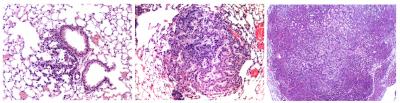

To better understand how these normally helpful components of the immune system are put to nefarious tasks in cancer cells, Verma and his colleagues developed a new method of inducing non-small-cell lung cancer in mice. This type accounts for as much as 80 percent of all lung cancer cases.

The researchers used a modified virus to insert genetic mutations into cells lining the mice's lungs, causing the animals to develop tumors. This laid the groundwork for studies on the molecular causes of this specific cancer type that would be impossible in humans.

To get around this limitation, the Salk researchers focused on IKK2, an enzyme that spurs NF-KB's activity in response to stress. When they blocked IKK2 activity in the mice with lung cancer, the mice had smaller tumors and lived longer, suggesting that the enzyme is necessary for NF-KB to stimulate tumor growth.

The researchers also showed that Timp-1, a gene involved in regulating cell growth, carries orders from NF-KB to tell lung cancer cells to proliferate. When they suppressed the expression of the gene, the mice with lung cancer had smaller tumors and survived longer.